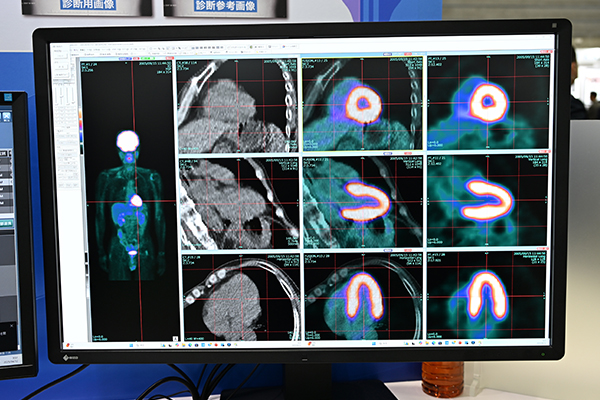

Imaging Solutionのコーナーでは,このほかに,核医学用画像融合システム「FUSION Plus」,PACS「XTREK F.E.S.T.A」のビューア「XTREK VIEW」,読影レポートシステム「LUCID」を紹介した。FUSION Plusは核医学検査とCT,MRIとのフュージョン画像を作成するシステム。「エクスポートコンソール」により,画像再構成の時間短縮,効率化を図れる。心臓核医学検査向けの機能としては,心臓サルコイドーシス診断のための「心臓三軸画像作成機能」を搭載。ワンクリックでの三軸画像の表示が可能である。さらに,FUSION Plusは,アミロイドPETにも対応。イメージング剤のメーカー各社が推奨するlook up table(LUT)を適用可能である。

核医学用画像融合システム「FUSION Plus」はワンクリックで心臓三軸画像の作成が可能